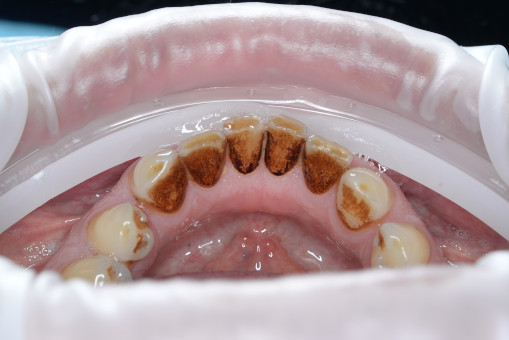

А прежде, чем вы посмотрите фотографии «до» и «после» лечения слизистой оболочки полости рта, проведенных в нашей клинике, хочу поблагодарить большое количество наших пациентов, которые поверили, прониклись нашей концепцией, и мы вместе, именно вместе победили болезни десны, гингивит и пародонтит!

До/после лечения